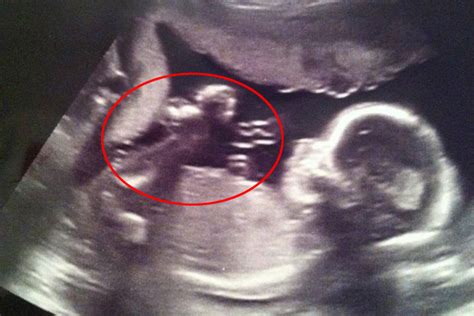

Prenataliniai genetiniai tyrimai ir tyrimai dėl įgimtų defektų apima nėščiosios ar vaisiaus vertinimą prieš gimdymą, siekiant nustatyti tam tikrų anomalijų, įskaitant paveldėtas ar spontaniškas genetines ligas, buvimą.

- Ultragarsas: Naudojamas vaisiaus matmenims matuoti, ypač nugaros odos raukšlės (nuchal translucency) matavimui.